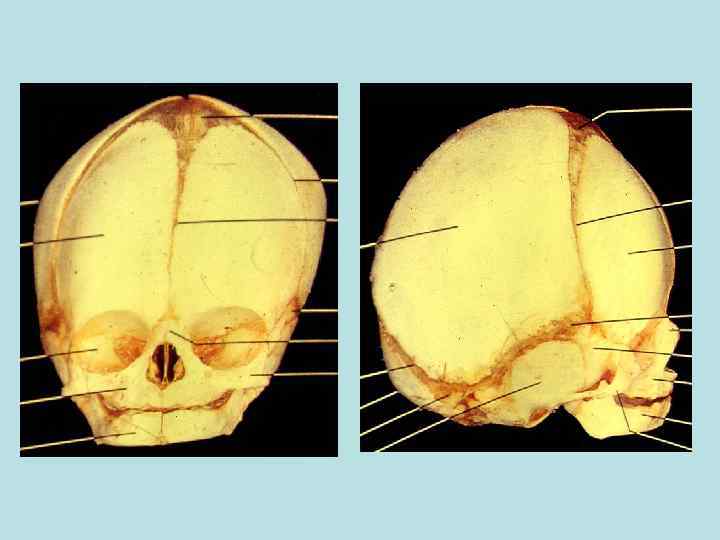

Принципы и направления современной анатомии • Принцип целостности организма уровни организации живого: - организменный (телосложение) - системоорганный (системы органов) - органный (органы) - тканевой (ткани: эпителиальная, соединительная, мышечная, нейральная) - клеточный ( клетки) - субклеточный (клеточные органеллы и корпускулярно-фибриллярно-мембранные структ. ) . Принцип развития (фило - и онтогенез, возрастная периодизация онтогенеза). Принцип единства строения и функции организма и его частей (функциональная анатомия). Принцип взаимосвязи организма и окружающей среды ( генотип и фенотип). Принцип единства теории и практики